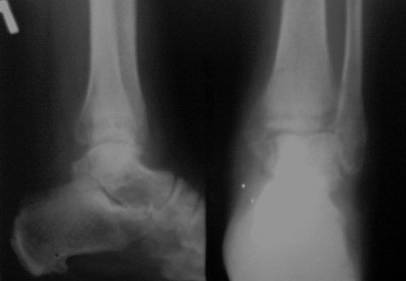

Здравствуйте,коллеги!Ко мне на консультацию обратилась больная 54 года,110 кг весом . травма 3 мес. назад , лечилась амбулаторно в гипсовой лонгете . Как поступить далее? Я планирую ORIF , внутреннюю лодыжку - спицами и проволокой , наружную - пластиной 1\3 трубки .Позиционный винт для фиксации синдесмоза. Как Вы считаете , это верная тактика ? какой вероятен исход ? Какие имеются нюансы в этом сроке , особенности техники? Может стоит вначале разработать движения в голеностопе ? Нужен ли гипс после операции ?

Имя     : через 3 мес..jpg